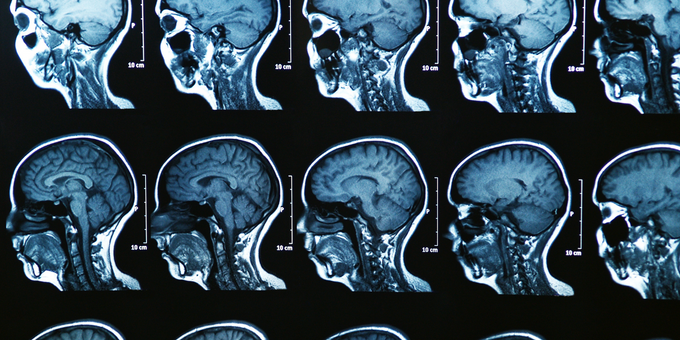

Frontotemporal dementia is a term used to describe diseases that result in the slow loss of brain tissue in the frontal and temporal lobes of the brain – this simply means the front, left and right sides. It’s responsible for almost 40% of early-onset dementia cases and is one of the most likely causes of the disease in those under 65 years of age. Unlike other forms of neurodegeneration, frontotemporal dementia usually develops slowly and it can take years for symptoms to become debilitating.

It occurs as a result of a build-up of abnormal proteins in the brain. One protein, known as amyloid, leads to a number of plaque deposits, as does another protein, known as tau – the plaque deposits of this protein tend to create tangles in and around our brain cells. The result includes changes in speech patterns, behaviour and even personality. Take a look at some of the symptoms of frontotemporal dementia – keep in mind some of these tend to show up in the later stages of the disease: